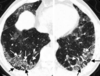

Nodule excavé dans un contexte de granulomatose de Wegener

Histiocytose X

Association

- Nodules irréguliers centrolobulaires

- Nodules troués

- Kystes

Prédominance régions supérieures